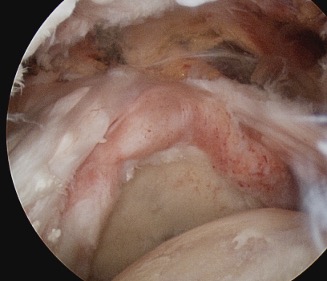

Tear patterns of supraspinatus and infraspinatus

| Crescent shaped | U shaped | L Shaped |

|---|---|---|

|

Small to medium tears Repair to footprint |

Large tears Need margin convergence then repair to footprint |

Antero-superior or postero-superior tears Need to mobilize cuff anterior or posterior |

![]() |

Crescent, U shaped and massive rotator cuff tears